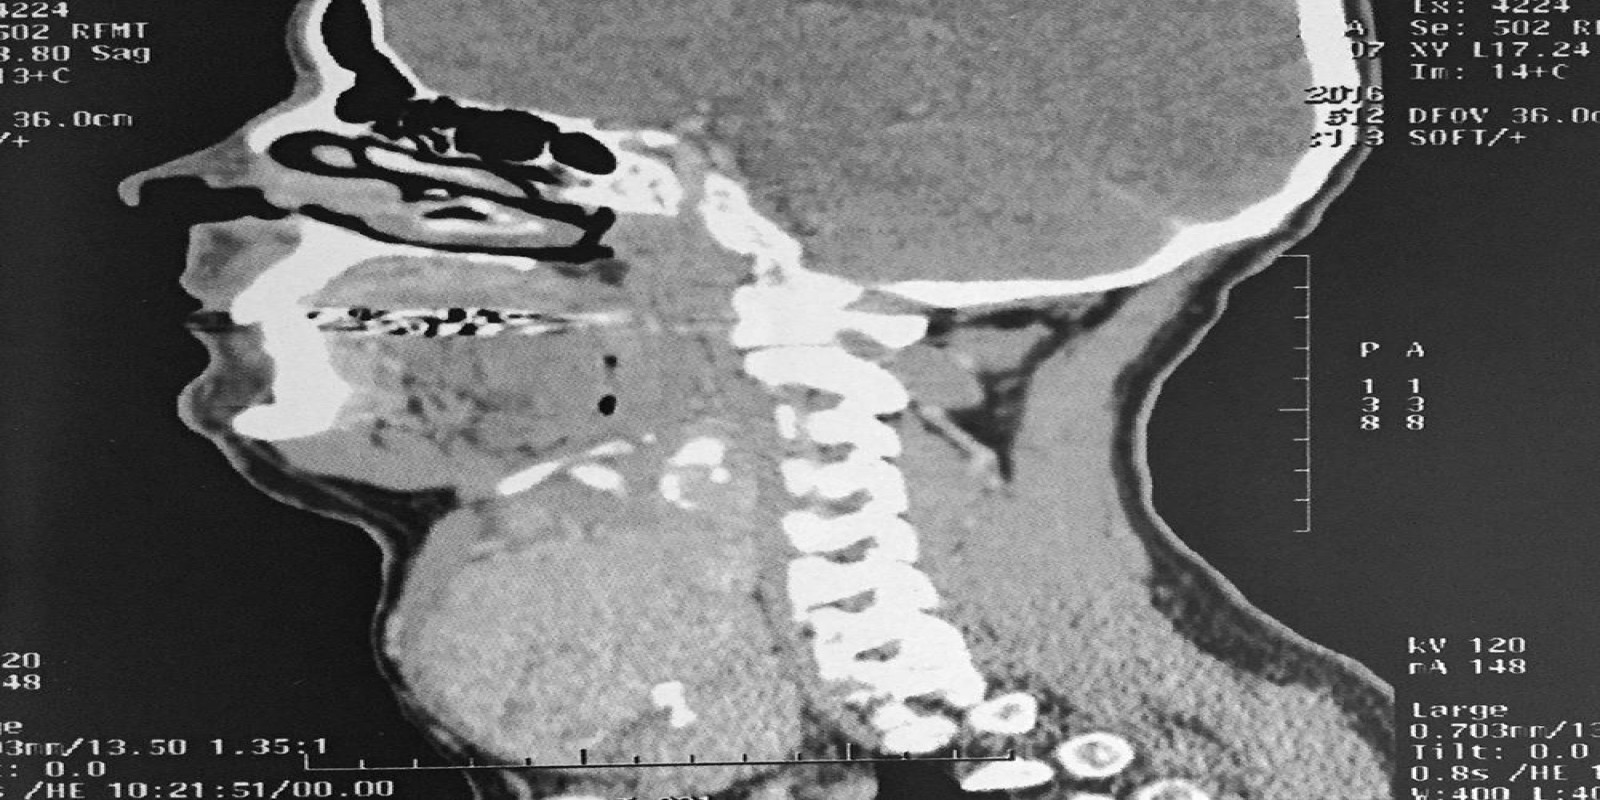

Caso Código 194B de Bócio Multinodular Atóxico

Cod.: 194B